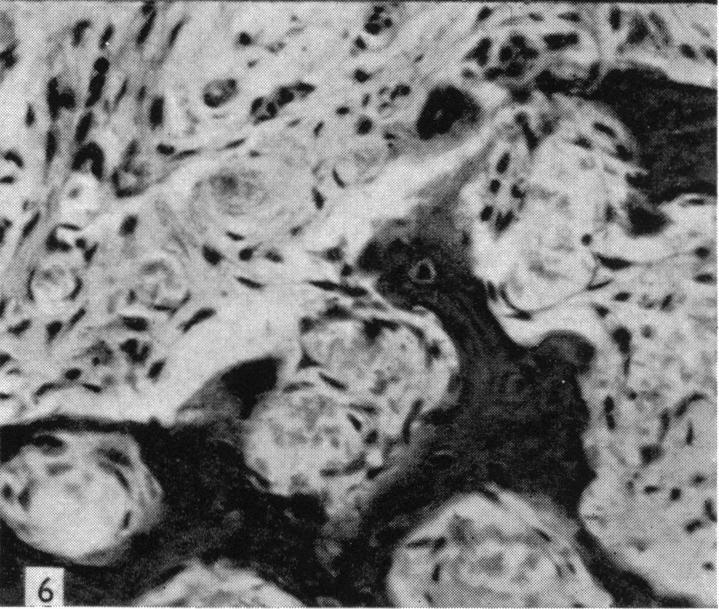

Alizarin as an indicator of bone growth.

J Anat. 1960 Jul;94(Pt 3):432-42.